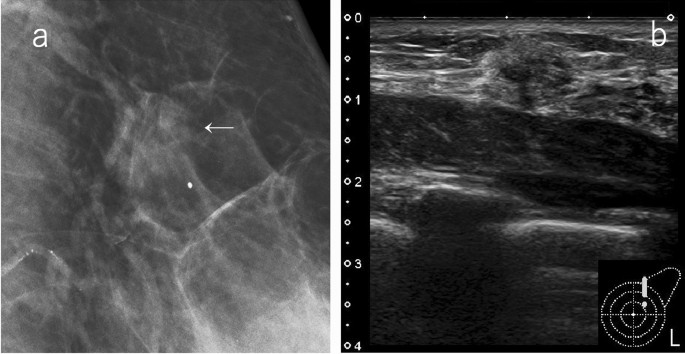

Examples of lesions that are visualized as circumscribed masses on mammography include cysts, fibroadenomas, intracystic tumors, and breast cancers with minor tendency to invade surrounding tissues (mucinous carcinoma, etc.). Ultrasound is useful for the evaluation of the internal structure or orientation of the mass, and if there are findings of simple cysts or typical fibroadenomas, ultrasound findings can be prioritized and classified as SC 2 (Fig. 2). Even when a benign tumor, such as a cyst or fibroadenoma, is hidden by superimposed or adjacent fibroglandular tissue, and appears to have obscured margins, it can be classified as category 2 by ultrasound.

A case of circumscribed mass on mammography. a Mammography: oval mass with margin mostly obscured but also circumscribed, SMC 3. b Ultrasound: oval, circumscribed, and parallel to the skin; classically fibroadenoma, SUC 2. The overall assessment category: SC 2 (SMC screening mammography category, SUC screening ultrasound category, SC screening category)